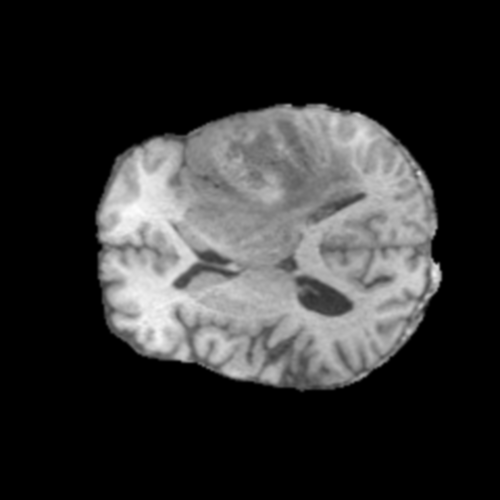

Glioma de Bajo Grado (LGG)

FLAIR LGG

FLAIR

T1ce LGG

T1ce

T2 LGG

T2

T1 LGG

T1

Núcleo LGG

Núcleo

Edema LGG

Edema

Realce LGG

Realce

Tumor Completo LGG

Tumor Completo

Núcleo Edema Realce

Ejemplos LGG - Atención Difusa en Edema Peritumoral

LGG Grad-CAM++ 1 LGG Grad-CAM++ 2 LGG Grad-CAM++ 3 LGG Grad-CAM++ 4 LGG Grad-CAM++ 5 LGG Grad-CAM++ 6

Para casos LGG, la atención del modelo es más difusa y se concentra principalmente en la región de Edema Peritumoral (verde), consistente con la naturaleza más infiltrativa y menos agresiva de estos tumores.